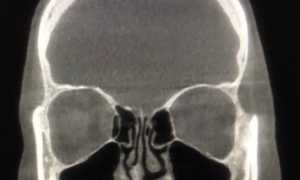

Заболевание также известно как “попугайная болезнь”: чаще всего им страдают хозяева домашних птичек. Болезнь является разновидностью хламидиоза, только он поражает центральную нервную систему и легкие. Человек может заразиться, вдохнув пыль, которая содержат хламидии. Для владельцев животных болезнь достаточно опасна, так как может привести к воспалению сердечной мышцы и тромбозу.

От кого можно заразиться: от попугаев, канареек, городских голубей и других домашних и диких птиц.

Симптомы у животных: от легких простудных проявлений до поражения органов пищеварения и дыхательной системы.

Симптомы у человека: интоксикация, температура, пневмония, насморк, слабость, боли в мышцах.

Лечение: антибиотики из группы тетрациклинов (вибрамицин, доксициклин и другие).

Профилактика: тщательно чистить и дезинфицировать клетки, но только в маске и перчатках, сократить обращение перьевой пыли. Если у животного появились симптомы заболевания, следует отнести его к ветеринару.